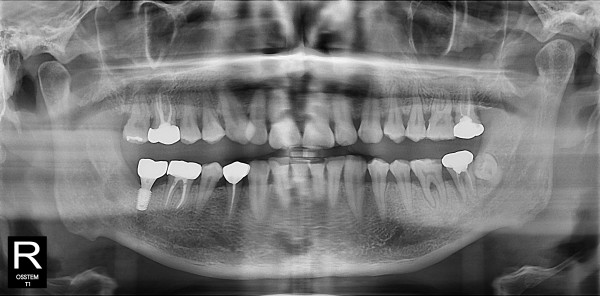

사랑니발치 30대/남성

5e20e086184bc11a2d853605b7813944_1764319927_9305.jpg